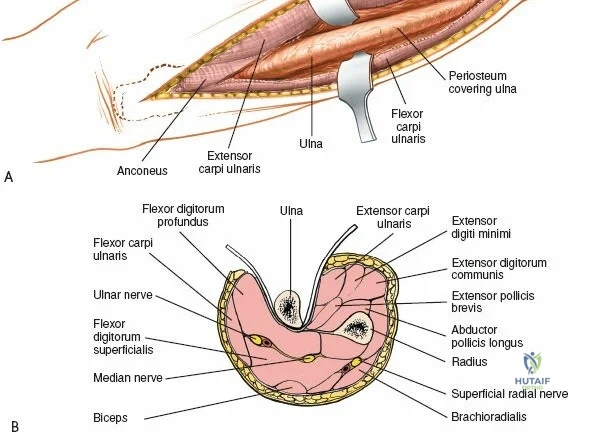

The surgical anatomies of the two bones of the forearm differ significantly, dictating vastly different operative strategies. The ulna features a subcutaneous border that extends for its entire length; the bone can be reached simply and directly via a straightforward approach without endangering major neurovascular structures. In stark contrast, the upper two-thirds of the radius are deeply enclosed by a complex, multi-layered sheath of muscles. Accessing the proximal radius requires a profound understanding of three-dimensional forearm anatomy, as the radius acts not merely as a static strut, but as a rotating lever arm essential for pronation and supination.

The posterior interosseous nerve is the single most important structure left vulnerable during exposure of the proximal radius. A branch of the radial nerve, the PIN dives into the supinator muscle through the Arcade of Frohse. It travels obliquely and spirally around the radial neck and proximal shaft within the substance of the supinator. In approximately 25% of patients, the nerve comes into direct contact with the posterior periosteum of the radial neck. Therefore, any blind placement of retractors around the posterior aspect of the proximal radius is strictly contraindicated, as it can easily crush the nerve against the bone, resulting in devastating loss of finger and thumb extension.

The proximal radius is draped by the supinator muscle. The PIN passes directly through the belly of the supinator. To protect the nerve, the forearm must be fully supinated. Supination dynamically rotates the radius, carrying the insertion of the supinator anteriorly and simultaneously displacing the PIN laterally and posteriorly, safely away from the surgical field.

With the forearm fully supinated, identify the broad insertion of the supinator on the anterior aspect of the radius. Incise the supinator directly along the line of its insertion onto the bone. It is critical to detach the muscle by dividing its insertion sharply at the bone, rather than splitting the muscle belly, which would risk cutting the PIN.

Proceed with strict subperiosteal dissection, elevating the supinator laterally off the bone. This is one of the rare instances in orthopedic surgery where the safety gained by staying in a subperiosteal plane completely outweighs the theoretical vascular damage to the bone caused by periosteal stripping. The elevated supinator muscle belly now acts as a protective cushion for the PIN.

Retractor Placement and Fixation Technique

Once the proximal radius is exposed, great care must be taken with retractor placement. Never place Hohmann or levering retractors blindly around the posterior surface of the radial neck. Because the PIN may touch the bone posteriorly in up to 25% of patients, a posteriorly placed retractor can easily crush the nerve against the radial cortex. Instead, use gentle right-angle retractors or place retractors only on the anterior and lateral aspects of the bone, utilizing the elevated supinator as a shield.